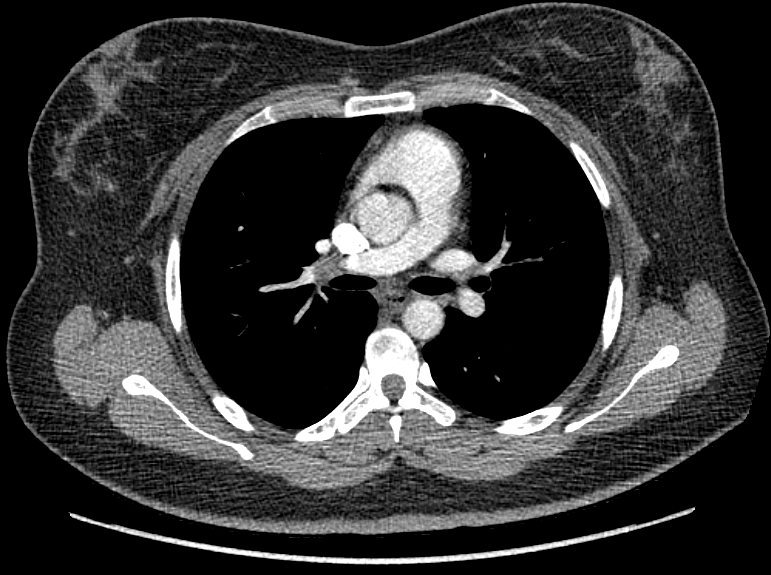

F/34

°Ç°­°ËÁø»ó ½ÃÇàÇÑ Chest PA »ó mediastinal widening ¼Ò°ßÀ¸·Î further evaluation À§ÇØ ³»¿øÇÔ.

Áõ»óÈ£¼Ò ¾øÀ¸¸ç ½Åü°ËÁø»ó ƯÀÌ¼Ò°ß ¾øÀ½.